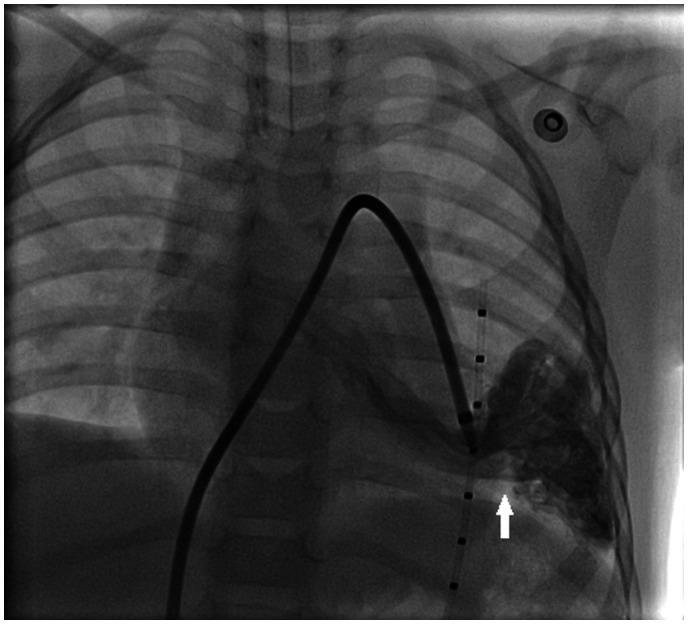

Eighteen months old female child was referred to our centre due to unexplained central and peripheral cyanosis. Based on the agitated saline contrast echocardiography study, computed tomography scan confirmed the presence of abnormal vasculature at the left lower lobe. Percutaneous closure of the PAVM was performed using Amplatzer Duct Occluder type 1 device. The genetic study revealed a pathogenic mutation in the endoglin gene, which is a known cause of hereditary haemorrhagic telangiectasia (HHT) inhered in an autosomal dominance pattern.

一名18个月大的女童因不明原因的中枢性和外周性发绀被转诊至我院。基于生理盐水对比剂超声心动图检查,计算机断层扫描证实左下叶存在异常血管。使用1型Amplatzer导管封堵器对PAVM进行了经皮封堵。基因研究显示内皮素基因存在致病性突变,这是常染色体显性遗传的遗传性出血性毛细血管扩张症(HHT)的已知病因。